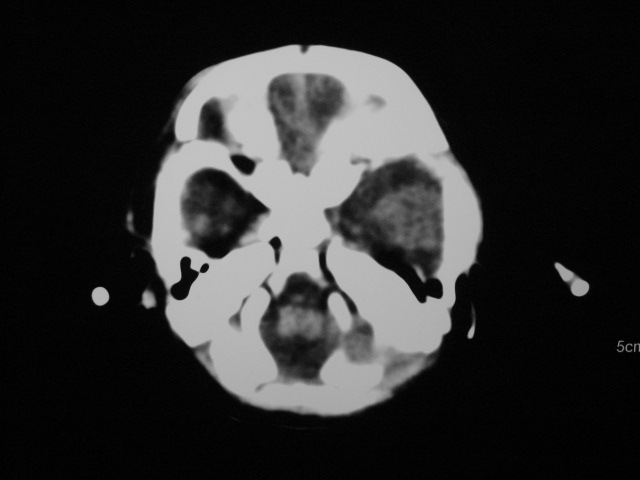

早产儿,1天,饮食呕吐,

支持;新生儿缺血缺氧性脑病伴少量蛛网膜下腔出血.

支持;新生儿轻度缺氧缺血性脑病伴少量蛛网膜下腔出血.

患儿头颅ct示:皮质薄,髓质密度减低,脑回宽,脑沟浅,脑室系统无殊,中线结构居中,符合:早产儿颅脑ct改变。